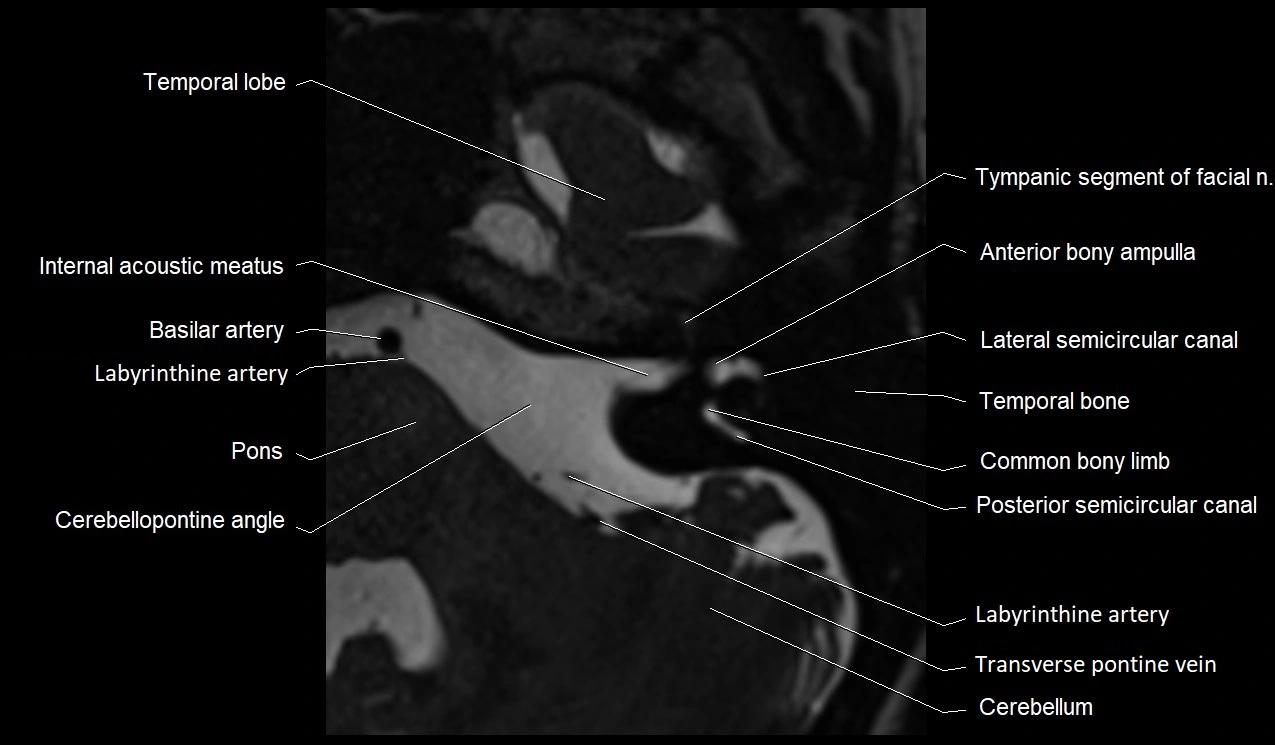

• Best visualized on high-resolution T2-weighted 3D MRI sequences (e.g., FIESTA or CISS)

• Seen as a hypointense (dark) line running from the brainstem at the pontomedullary junction, traversing the prepontine cistern, and entering Dorello’s canal under the petrosphenoidal ligament, then into the cavernous sinus, and finally the orbit